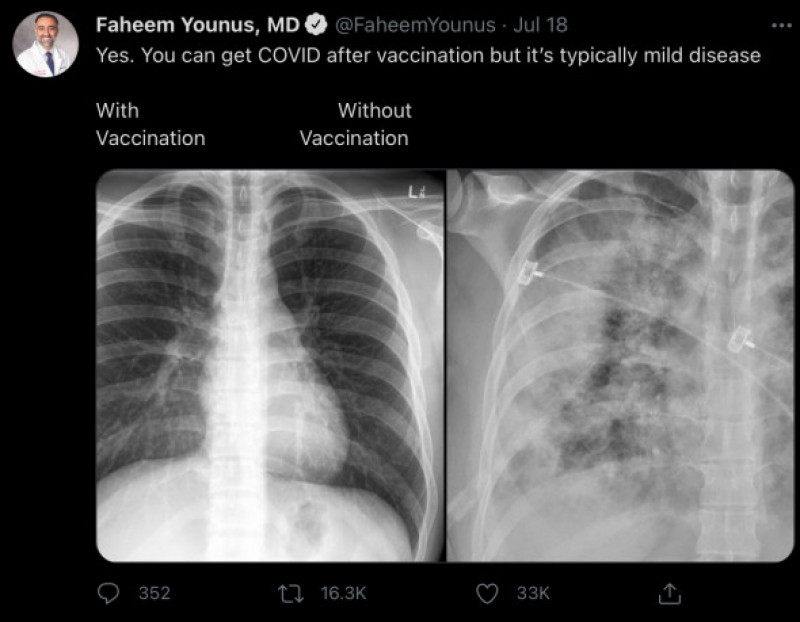

Un medic din SUA, specializat în medicină internă și boli infecțioase, a arătat, cu ajutorul unor radiografii pulmonare a doi pacienți Covid-19, care este diferența dintre plămânii unei persoane vaccinate și ai alteia neimunizate împotriva virusului, scrie digi-world.tv.

Dr. Faheem Younus a explicat că și cei vaccinați pot face forme ușoare de coronavirus, însă cei care nu s-au imunizat pot avea probeleme grave și au risc mare de a ajunge la Terapie Intensivă, mai ales acum, când tulpina Delta devine predominantă în multe zone ale lumii.

Yes. You can get COVID after vaccination but it’s typically mild disease

„Da, puteţi să vă îmbolnăviţi de COVID-19 dacă v-aţi vaccinat, dar de obicei este vorba despre o formă uşoară”, este comentariul medicului Faheem Younus, care însoţeşte fotografia cu două radiografii pulmonare, pe care acesta a pus-o pe Twitter.

Plămânii pacientului vaccinat apar în partea stângă a imaginii, fiind mult mai negri decât cei din radiografia din dreapta, cea a unui pacient neimunizat și foarte afectat de puterea virsuului Sars-CoV-2.